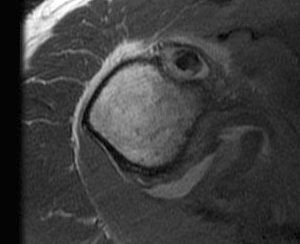

Tendonitis / tendinopathy

Normal

Tendonitis

Tendon thickening / tendinopathy

Sagittal MRI demonstrating severe LHB tendinopathy